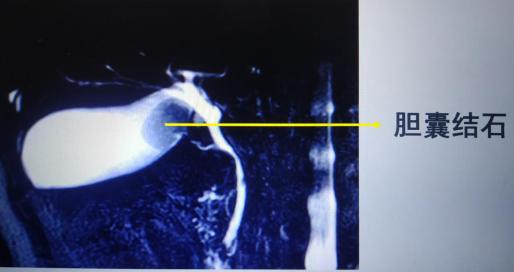

此时首选B超确定诊断,根据结石部位不同可见胆管扩张、结石影像、胆囊增大等,若诊断不清还可选用CT、MRCP(磁共振胆胰管成像)等检查。